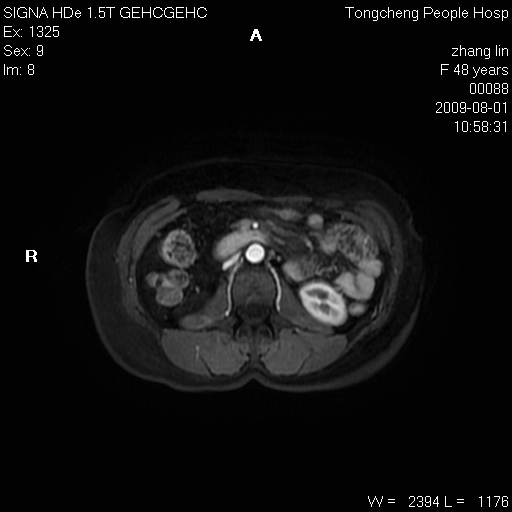

女,48岁。健康体检,彩超发现右肾占位性病变。平素健康。

临床诊断:右肾占位性病变,性质待定(囊肿?肿瘤?)。

上中腹部mr平扫+增强扫描,图像如下:

右肾上极见一类圆形病灶,t1wi呈等信号t2wi呈等高混杂信号,三期增强无强化,边界清---考虑囊肿出血。

同反相位均表现为等信号,病变无强化,考虑含蛋白的囊肿可能,弥散加权相或许有些帮助,

慢性胆囊炎